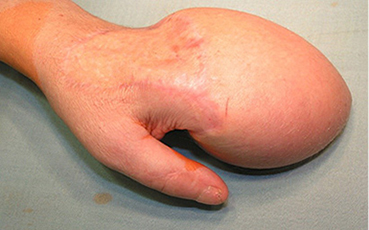

5 pav.

6 pav

7 pav.

8 pav.

Vaizdas po I rekonstrukcijos etapo. Prigijęs kirkšnies lopas vėliau atskirtas nuo donorinės vietos ir perskeltas tarp III ir IV pirštų, suformuojant dviejų pirštų kompleksus. Stebimas minkštųjų audinių perteklius, ypač ties IV pirštu, kur buvusi lopo „kojytė“ ir darbiniame suformuoto piršto paviršiuje atsivėrusi opelė (5–8 pav.)